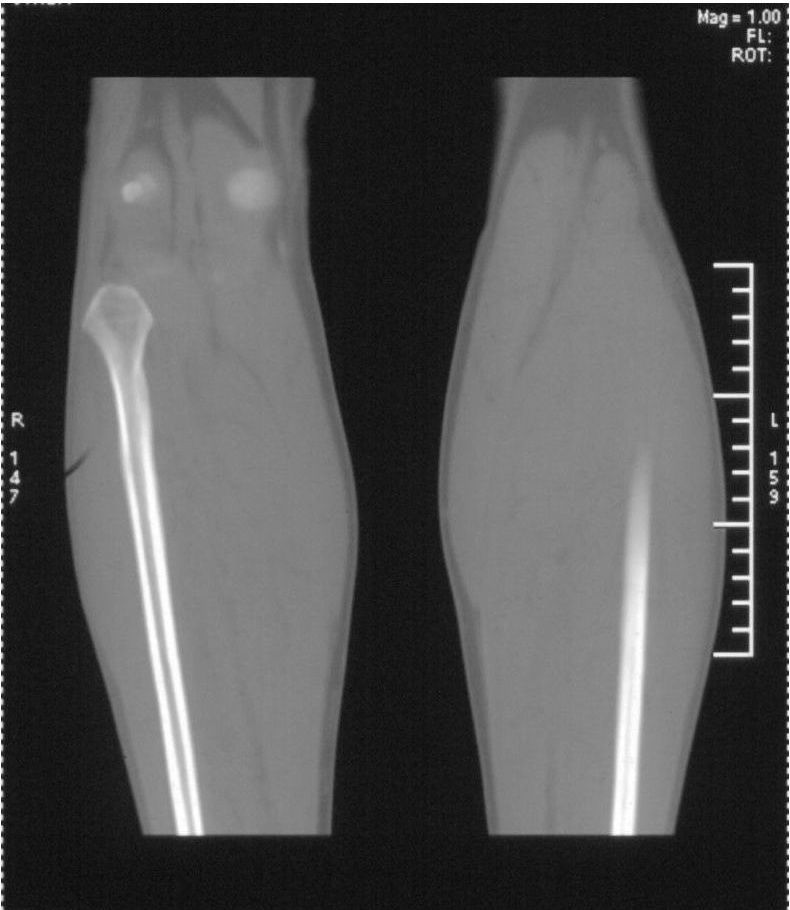

男,42岁。4个月前钢筋钝伤右侧小腿部,当时因无明显外伤,未引起重视。一周后因受伤腿部疼痛,发现肿胀,随后到当地医院进行检查(2008年4月16日)。因未发现骨质异常未引起重视,仅仅进行口服抗生素治疗处理。经过一段时间治疗但未见明显治疗效果在5月29日又进行x线检查,发现有胫骨密度上段密度增高,又进行抗炎治疗,仍未见效果。又在7月3日进行x线检查,仍然报告有胫骨上端密度增高,并建议ct检查。以下是相关检查结果:

髓腔密度呈絮状增高,胫骨上端内侧可见层状骨膜反应,考虑骨髓炎.

髓腔密度呈絮状增高,胫骨上端内侧可见层状骨膜反应,肌间隙模糊,考虑骨髓炎.

破坏、增生、骨膜反应,考虑骨髓炎